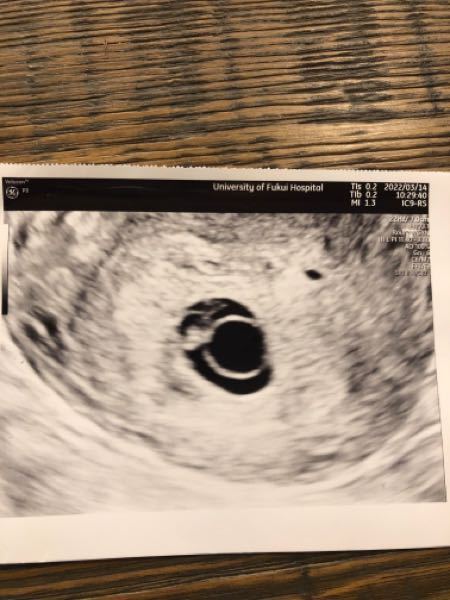

今日は稽留流産手術の日です 昨晩は、旦那と二人で、お腹の中の赤ちゃんに 「また近いうちに会いに戻ってきてね」ってお別れを言いました。 心拍停止の診断から5日が過ぎ、ずいぶん心も落ち着いてきました。 手術までの猶予期間って、ほんとに大事です。 そして今日は、旦那も一緒 セカンドオピニオンでわかった妊娠初期の赤ちゃんの心拍停止と稽留流産に対する医師の考えの違い。 kaipapa 19年7月2日 18年7月下旬、妊娠9週目、3回目の通院で僕たちの赤ちゃんの心拍が確認できないと言われました。(そのときの記事は「妊娠9週目で赤ちゃんの心拍が確認できなくなった 稽留流産の診断から一転、心拍や胎児の成長が認められることはありますか? 2月の初旬に尿検査と経膣エコーにより妊娠の診断を受ける。(大きさから約6wといわれる。) 2週間後に予定日などを決めましょうと言われ、2週間後に受診。 経膣エコーで胎嚢を確認するも胎児がうっすらとし

心拍確認後、11週の健診の日に稽留流産がわかりました。 稽留流産とはどのようなものか、そして、私の体験談を紹介します。 目次 表示 流産とは妊娠22週未満で妊娠が終了してしまうこと 稽留流産とは? 読み方は「けいりゅうりゅうざん」 流産・心拍も確認できない なので稽留流産でしょう、という説明を受けました。 出血があったということ以外は特に変わったこともなかったので、その診断にはとてもショックを受けました。 何も考えられない私に、お医者さんは稽留流産というものについて説明をしてくれました。 その時は全� 9週での稽留流産。 腹痛・出血で救急車で運ばれ掻爬手術をした話 こんにちは、ショコハジロです。 突然ですが 先月末に9w2dの大きさで赤ちゃんを稽留流産をしました 。 一度心拍を確認できた後の出来事だったので、このまま順調に行くのだと思ってい

・心拍確認後の稽留流産 ・最後の心拍確認から4週間後、流産手術 流産兆候① 出血 6週0日 → 茶オリ。量は少ないけど3日間続いたので病院に相談。「初期にはよくあること、問題ナシ」と言われる。すぐ止まった。 11週1日 → 自分では気づかなかったけど、検診で内診が始まった瞬間「中 胎芽が見えなかったけど繋留(稽留)流産じゃなかった話 こりのろっさ 16年11月日 / 18年10月30日 12 妊娠中はいろいろなトラブルに見舞われまして、貴重な体験を数々してきました。 今回は胎芽が見えなくて繋留(稽留)流産と言われたけど稽留流産の手術をするかどうかのセカンドオピニオンを聞きにきた総合病院。 内診でまさかの心拍確認。 身体の震えが止まらず内診室から診察室に戻りました。 「確かに大きくなっているようだし心拍も見えましたね。こんなことあんまりないんだけどね。